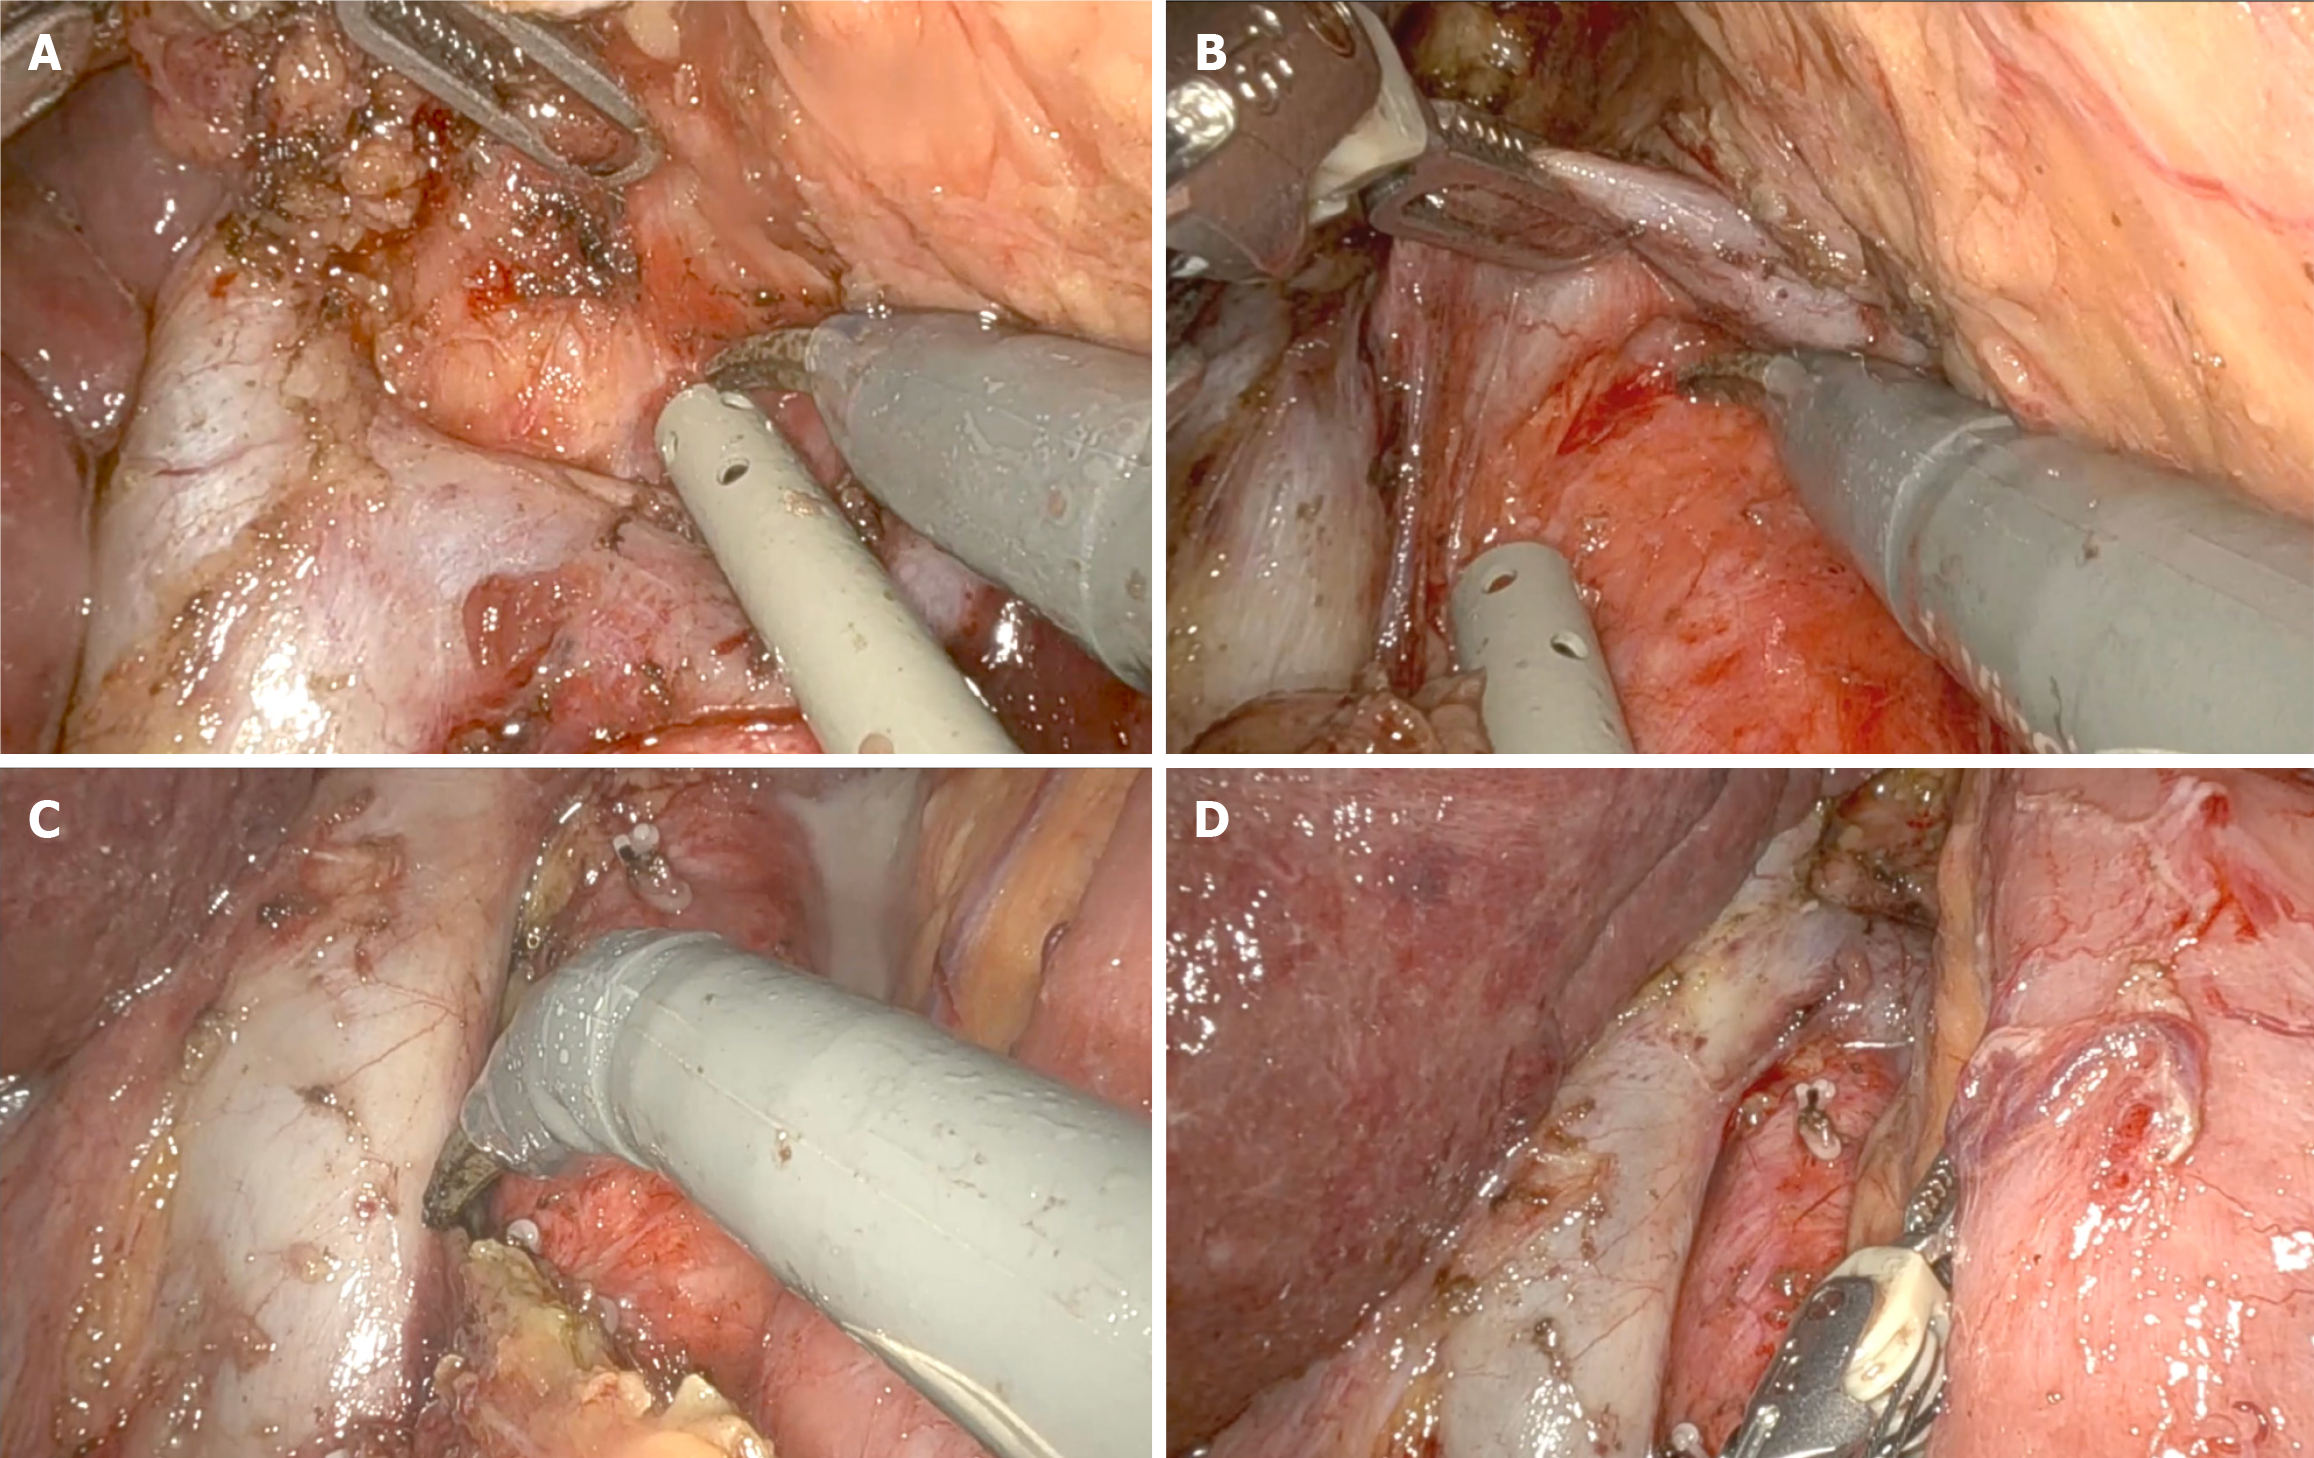

Previous reports have shown improved 3-year survival with robotic gastrectomy in patients with stage I/II GC[46]. It is generally accepted that the robotic approach can provide accurate lymphadenectomy, allowing better staging of the disease[47,48]. A recent update of the Italian Research Group for Gastric Cancer database shows a strong correlation between removed and positive lymph nodes, with this relationship reaching a plateau when 40-50 lymph nodes are examined. It suggests that survival for patients with the same number of metastatic nodes is significantly influenced by the total number of nodes removed: 12% for less than 10 nodes, 26% for 11 to 15 nodes, and 60% for more than 25 nodes[31]. As the number of lymph nodes harvested can be a predictor of survival, more extensive lymphadenectomy (i.e., removal of para-aortic and/or posterior nodes) may be indicated in GC with a high risk of extraperigastric metastases, such as located in the upper third of the stomach, with serosa involvement or exhibiting bulky nodes in the second level perigastric nodal stations[10]. No statistical differences in morbidity, mortality rates and mean hospital stay were observed compared to D2 lymphadenectomy[49]. The robotic system allows to mimic open surgical principles to perform more extended lymphadenectomy, including para-aortic nodes. In a Chinese RCT (283 patients in one high-volume hospital), more extraperigastric lymph nodes were retrieved in the robotic assisted distal gastrectomy group (RADG) (17.6 ± 5.8) than LADG (15.8 ± 6.6), particularly in the para-aortic stations (Figure 1). The noncompliance rate, defined as the absence of nodes from more than one station that should have been excised, was lower (7.7% vs 16.9%)[50]. Interestingly, the RADG group showed less intense inflammatory responses and fewer postoperative complications (9.2% vs 17.6%), resulting in faster postoperative recovery and earlier initiation of adjuvant chemotherapy.

A known problem with MIS is pancreatic fistula caused by blunt trauma from compressing the pancreas and thermal injury from continuous use of energy devices[51]. A higher incidence of pancreatic fistula was described for laparoscopic approach when compared with robotic assisted (22.5% vs 10%)[52]. Assuming that this is probably related to the higher rate of pancreatic injury during lymph node dissection at stations 6, 8a, 9, 12, and 13, the highly articulated instruments and the possibility of retroversion facilitate the access to these stations better than the retraction of the human first assistant can guarantee (Figure 2)[53]. Similarly, a Japanese trial (236 patients in two institutions) reported fewer overall (8.8% vs 19.7%) and major (5.3% vs 16.2%) complications with the robotic approach, with no cases of pancreatic fistula and a similar rate of intra-abdominal infectious complications[54].